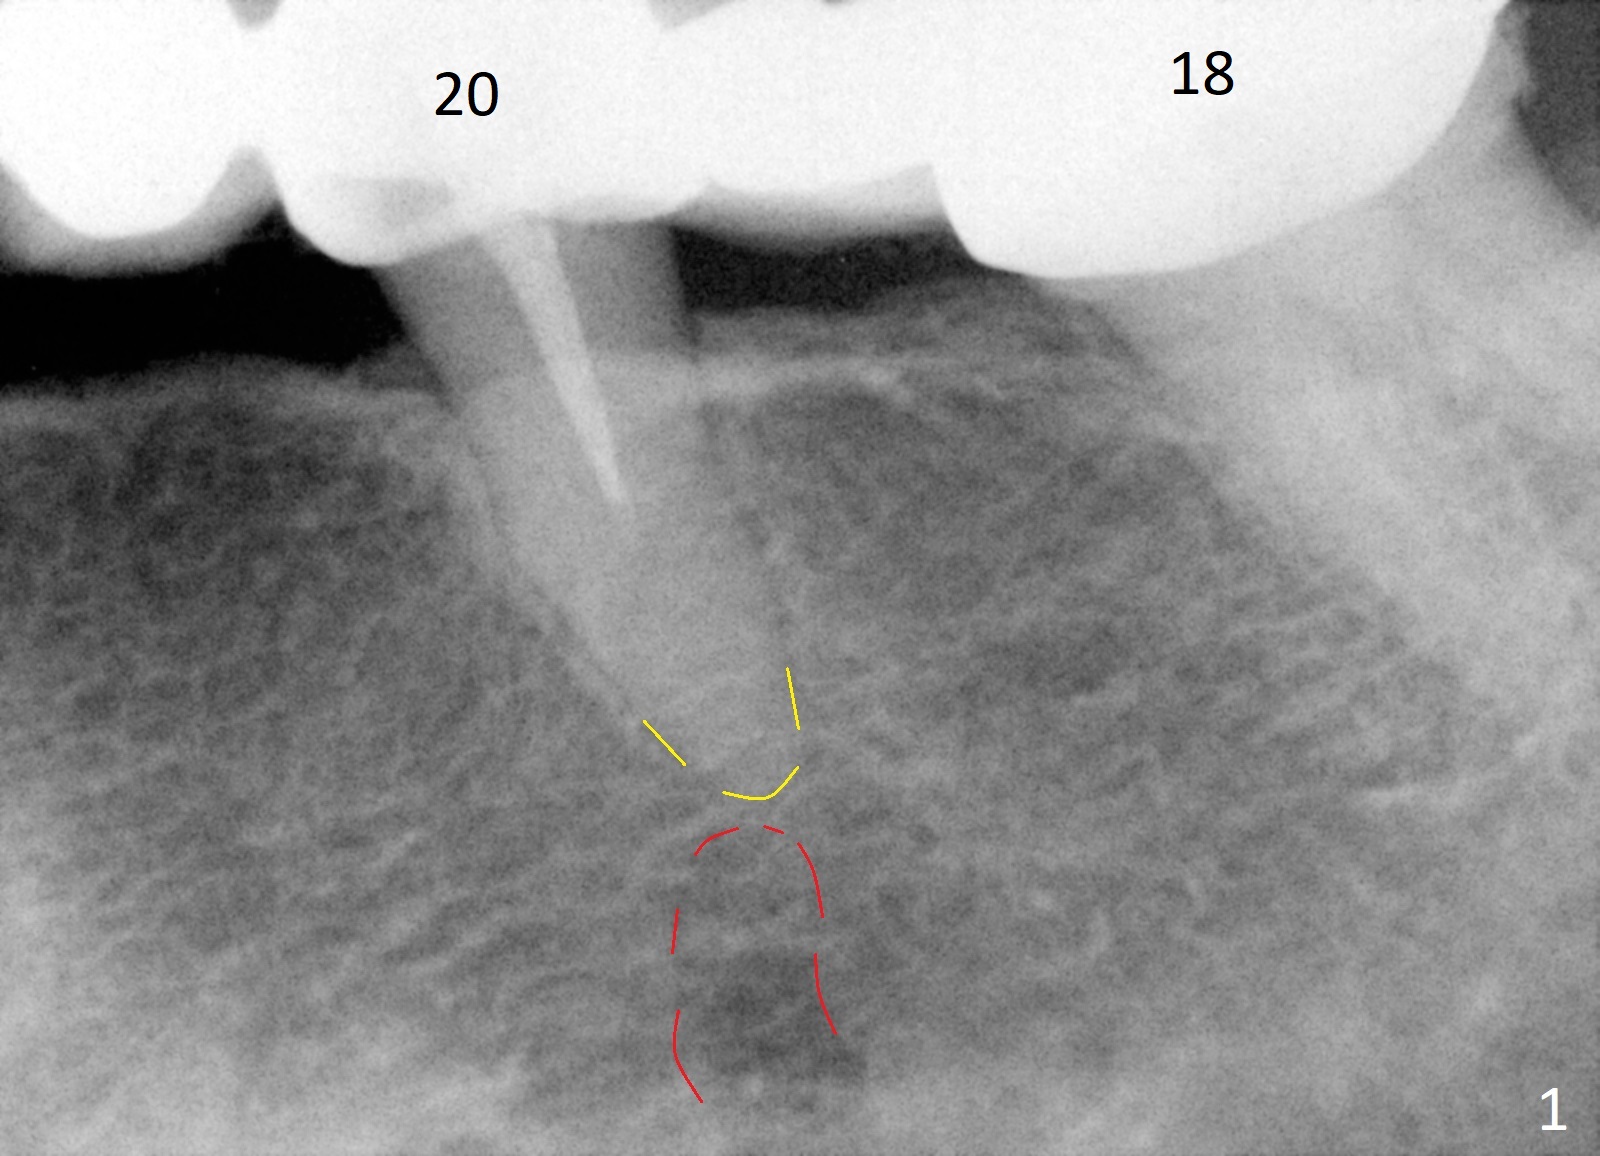

A 65-year-old woman used to have a long bridge (Fig.1). First, the portion mesial to #20 was sectioned. But the remaining portion kept chipping. RCT was retreated for the tooth #20 as the first step to have separate crowns at #18 and 20 and have a lower partial redo. Instead a new FPD was done between #18 and 20 in her own country (Fig.2). Two years later, the tooth #20 became symptomatic with increased pdl mesially (Fig.3*). Periradicular radiolucency increases in another 2 years (Fig.4). The apex of the affected tooth (yellow dashed line) is close to the Mental Loop (red dashed line, Fig.1-3). Although the loop is buccal to the apex of the 2nd premolar, an implant will not extend past the apex to avoid neuropathy (Fig.5). No Inferior Alveolar Nerve block will be administered. PA will be taken after pilot drill. The FPD will be sectioned between #18 and 19. To compensate for the short length of the implant, try to place a large one as long as the buccolingual bone allows. Adapt the lower RPD to the immediate provisional, which should be as small as possible, since the retention must be not too high.